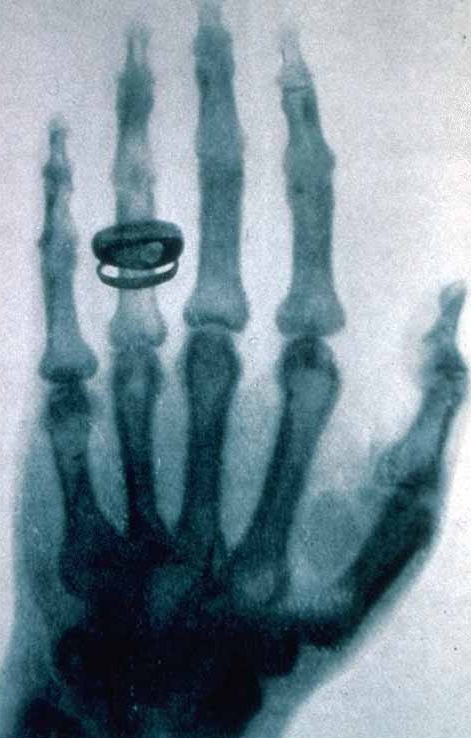

La première étape de cette épopée est la découverte des rayons X par Röntgen en 1895. Dans les mois qui suivent, les rayons X démontrent leur potentiel remarquable dans le domaine médical. Mais c’est seulement grâce à Laue et Bragg que ces rayons, grâce au phénomène de diffraction des rayons X par les cristaux, se révèlent être également un moyen très puissant pour explorer les structures cristallines. Ces découvertes de Laue et de Bragg marquent ainsi le début de la cristallographie moderne.

Première radiographie par Röntgen (la main de sa femme)